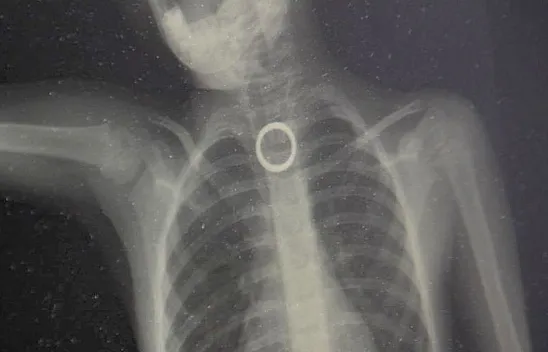

Son Dakika 23 Elazığ Haber Güncel 3 yaşındaki çocuk ölümden döndü PAYLAŞ 09.08.2022 11:18 Güncelleme: 09.08.2022 12:01 TAKİP ET İlgili Haber 3 yaşındaki çocuk ölümden döndü 3 yaşındaki çocuk ölümden döndü Elazığ'da 3 yaşındaki çocuğun yutması sonucu yemek borusuna sıkışan yüzük, yapılan cerrahi operasyonla çıkartıldı.